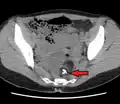

A complex cyst due to a dermoid as seen on ultrasound -

A complex cyst due to a dermoid as seen on CT. Arrow points to bone or teeth.